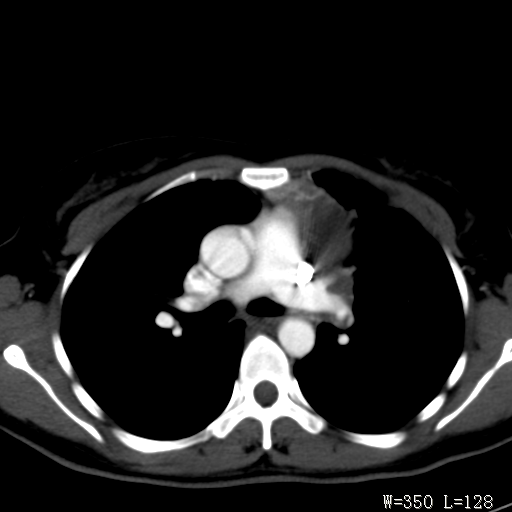

标题: CT27017:1、肺结核?2、永存左上腔静脉。 [打印本页]

标题: CT27017:1、肺结核?2、永存左上腔静脉。

女,32岁,自述肺结核治疗多年复查。

1)考虑左肺上叶肺脓肿,节段性肺不张。2)永存左上腔静脉。

1)考虑左肺上叶节段性肺不张。原因?2)永存左上腔静脉。

支持肺脓肿;还是双上腔静脉确切些吧,回流至冠状窦或右心房。

考虑左肺上叶胸腺瘤可能性大。肺不张/永存左上腔静脉

胸骨后偏左侧囊实性病灶,考虑胸腺瘤可能性大.

1、胸骨后偏左侧囊实性病灶,考虑胸腺瘤可能性大。2、永存左上腔静脉。